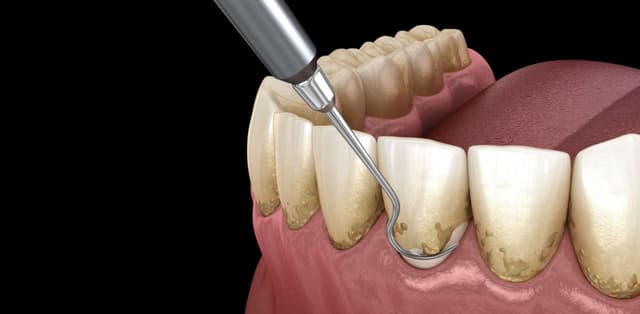

Theo các chuyên gia nha khoa khuyến khích, tốt hơn hết, bạn nên lấy cao răng khoảng 6 tháng/lần. Vậy cụ thể lợi ích của lấy cao răng là gì, cùng tìm hiểu bài viết để được giải đáp bạn nhé! 1. Giới thiệu sơ lược về biện pháp 15 Cao răng (hay còn gọi […]

Chúng ta nghe nhiều về cụm từ “cao răng” nhưng không phải ai cũng hiểu rõ hệ lụy mà cao răng gây ra đối với sức khỏe răng miệng. Do vậy, các bác sĩ nha khoa luôn khuyến cáo mọi người cần lấy cao răng thường xuyên. Vậy, lấy cao răng có tác dụng gì […]